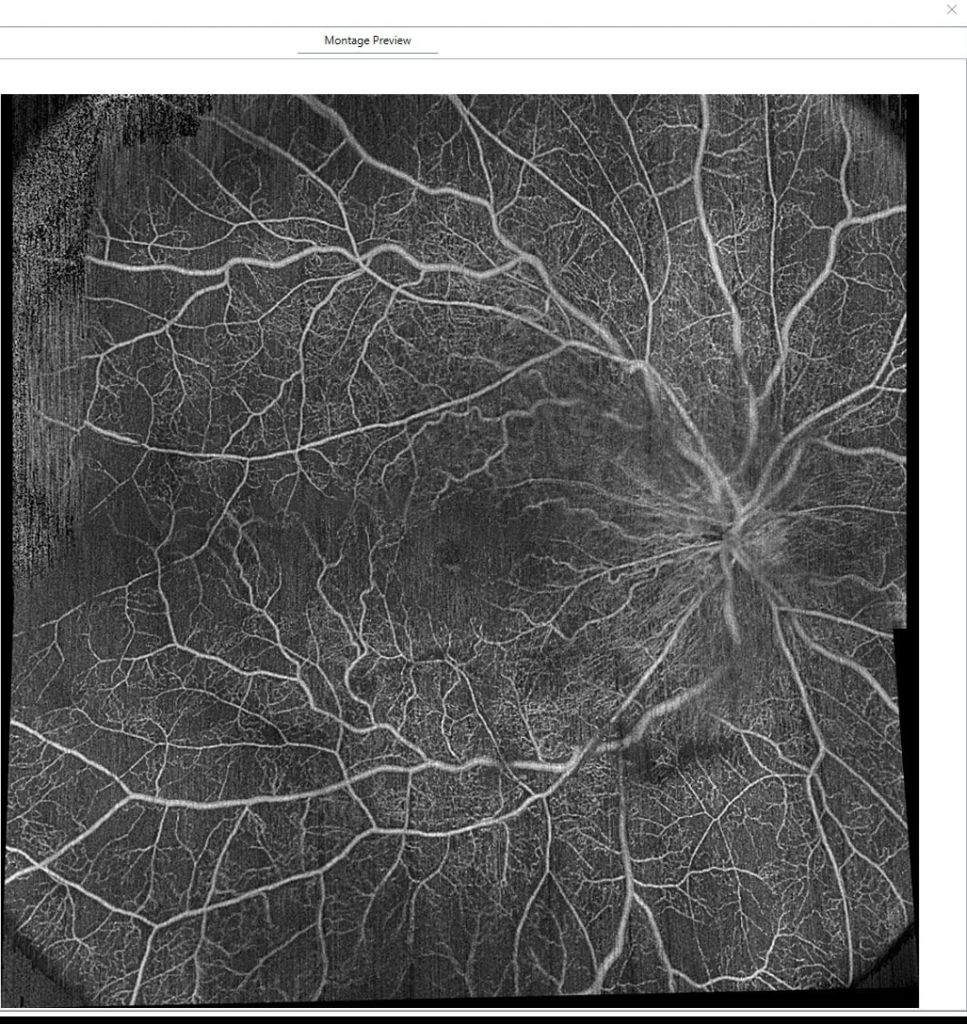

視神経乳頭中心に放射状に静脈に沿って火炎状・線状出血が網膜全体にみられる。

抗VGEF(ラニビズマブ)の硝子体注射2日後。